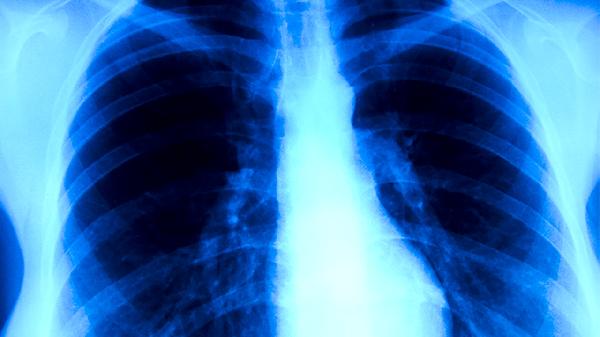

肺癌的中医疗法和西医疗法通常没有冲突,但需在医生指导下结合使用。中医治疗侧重整体调理和症状缓解,西医治疗以手术、放疗、化疗等直接干预为主,两者协同可提升疗效。

中医治疗肺癌常用益气养阴、化痰散结等法,如黄芪、白花蛇舌草等中药可减轻放化疗副作用,改善患者生存质量。西医治疗中,手术适用于早期肺癌切除病灶,放疗和化疗可控制肿瘤进展。靶向药物如吉非替尼片、奥希替尼片等针对特定基因突变效果显著。免疫治疗通过激活机体免疫系统对抗肿瘤。部分中药可能影响西药代谢酶活性,如华法林与丹参联用需监测凝血功能。

肺癌患者接受中西医结合治疗时,应避免自行配伍用药。中药煎剂与靶向药物间隔2小时服用可减少相互作用。放疗期间使用活血化瘀类中药可能增加出血风险,需谨慎评估。含重金属的中成药与化疗联用可能加重肝肾负担。建议由肿瘤科与中医科医师共同制定方案,定期复查肝肾功能及血药浓度。

肺癌患者日常需保证优质蛋白和维生素摄入,如鱼肉、西蓝花等,避免辛辣刺激食物。适度进行八段锦、散步等低强度运动,维持心肺功能。保持居住环境通风,减少油烟及粉尘接触。定期复查胸部CT和肿瘤标志物,及时调整治疗方案。心理疏导有助于缓解焦虑情绪,家属应关注患者情绪变化并提供支持。